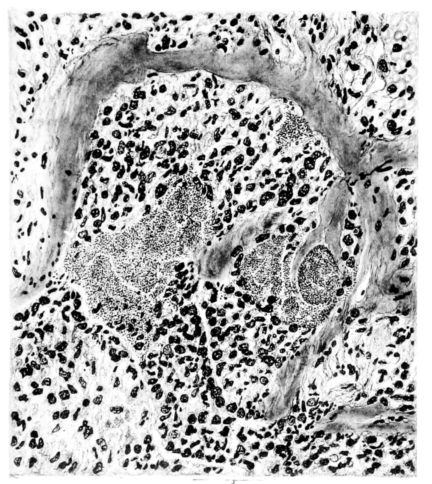

FIG. II. AUTOPSY NO. 98. DRAWING OF A SECTION THROUGH A TRACHEA SHOWING NECROTIZING HEMORRHAGIC INFLAMMATORY PROCESS OF THE MUCOSA.

The changes are less marked, perhaps, in the trachea than in its finer ramifications. The mucosa is constantly more or less destroyed and large areas, usually focal, are entirely devoid of their epithelial covering. This is replaced by a sparse exudate, composed largely of red blood cells, mucus, a small amount of fibrin, and nuclear fragments (Fig. II). It may dip into the submucosa for a short distance, but usually these indentures are associated with the ducts of the mucous glands into which the inflammatory reaction extends. A more striking feature than the exudate, however, is the edema and the congestion of the submucosa. The loose areolar tissue of the submucosa is spread widely apart, and throughout it distended blood vessels are very conspicuous. Occasionally such a vessel is broken and actual hemorrhage appears in the submucosa. Occasionally, too, the inflammation extends down the duct to the mucous gland itself, and here, also, aplastic inflammatory reaction is evident, inasmuch as the acini now stain intensely red with the cells undifferentiated from each other and specked here and there by broken remains of the dead nuclei (Fig. III). After the disease has continued for a short period, even at the end of five or six days, some regeneration of the epithelial lining may be seen (3) (Fig. IV). But despite this, the acute picture persists, and there goes on, side by side, an attempted repair characterized by epithelial regeneration and the same evidence of acute change. Since the lesion is essentially a superficial one, scars or contractures of any extent are not encountered in the trachea, even in examples of the disease that have ended fatally only after many weeks.[4]